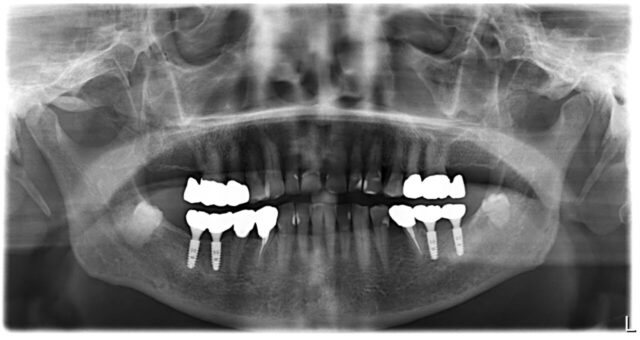

After

9ヶ月後,パノラマ写真

骨吸収もなく,経過良好です.

何でも食べられるそうです.